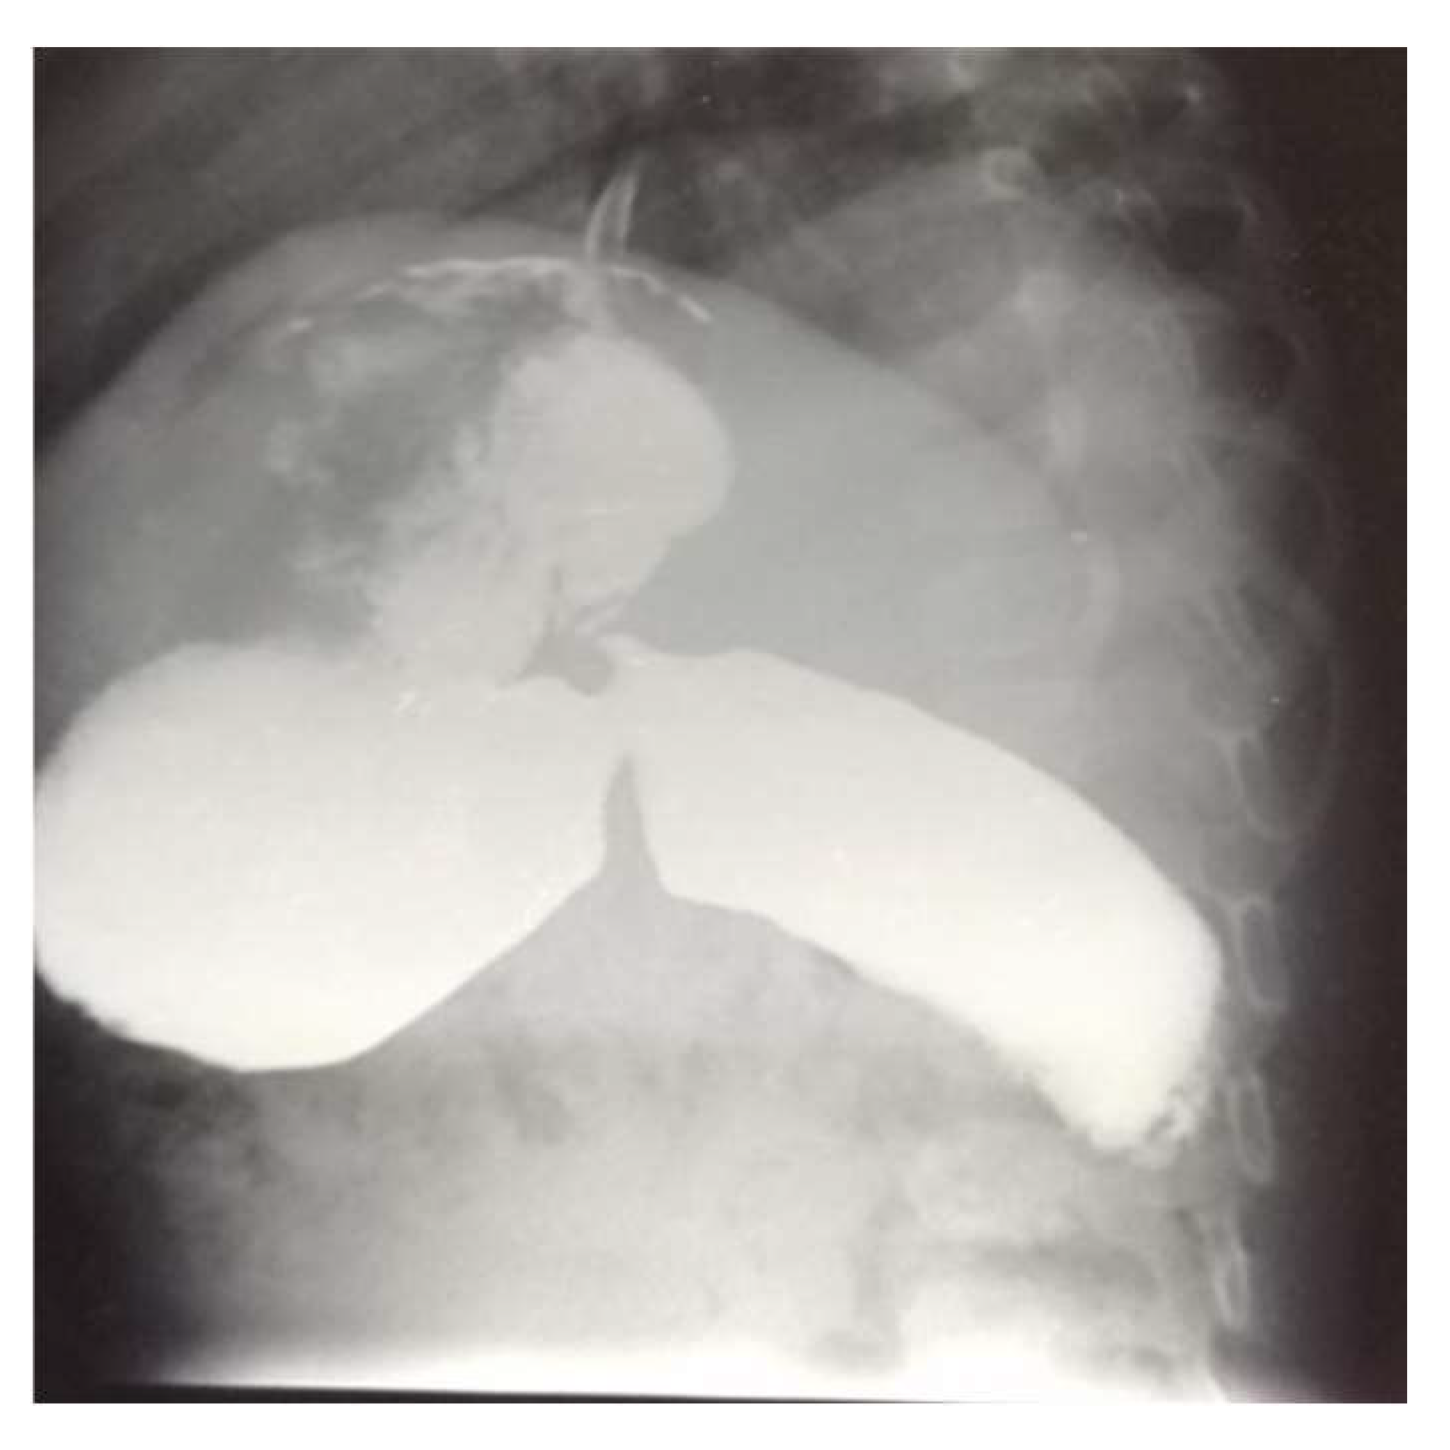

2. Case Presentation